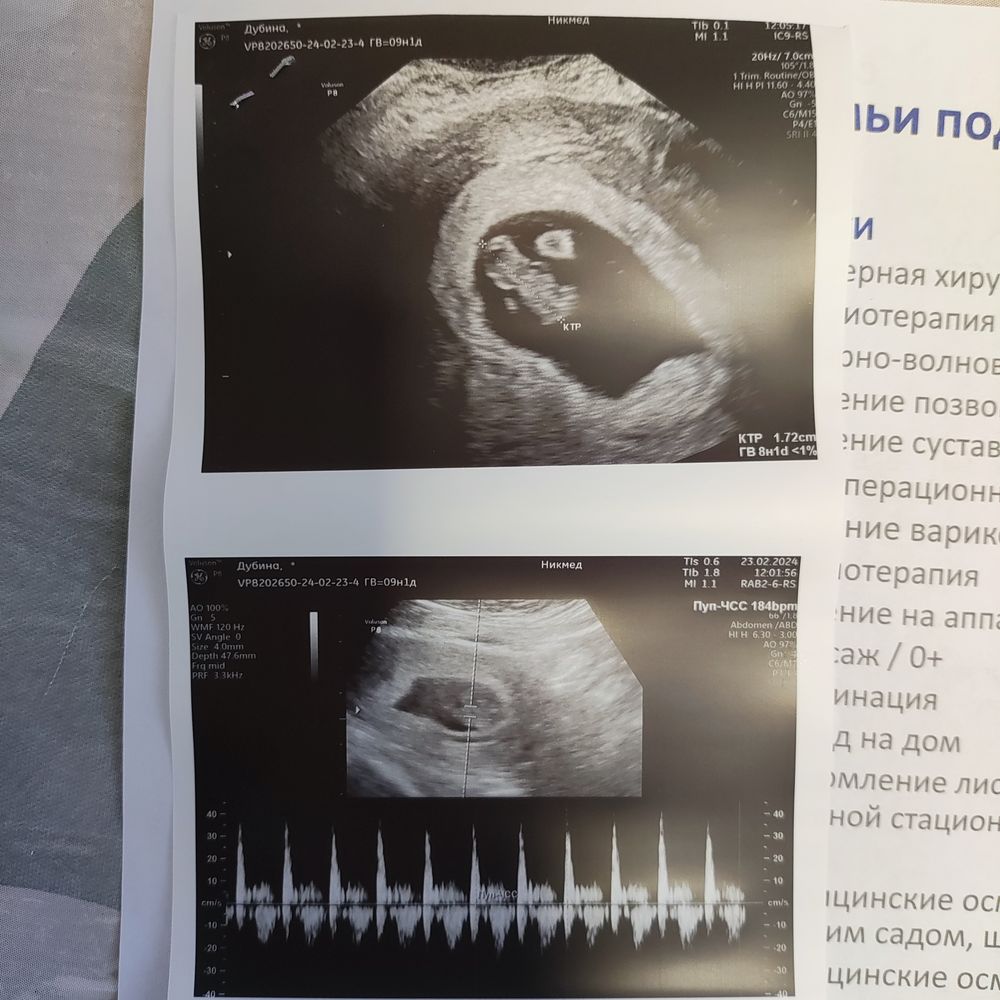

УЗИ 8 недель

Долго он всматривался в монитор, а потом включил мне сердечко! Лялик уже 17 мм, в понедельник был 12. Подросло мое чудо.

Сердечко 184 удара в минуту, узист сказал, что по верхней границе нормы.